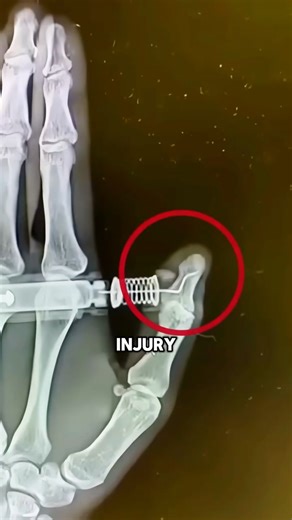

EpiPen Accidental Injury

130.1K amharc

6 Feabh 2015

YouTube

Larry B. Mellick, MD